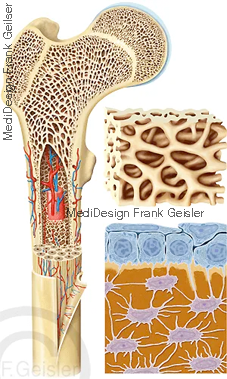

Körper mit Skelett, Darstellungen der Wirbelsäule; Lamellenknochen mit Knochenmark; Knochengewebe mit Osteoblasten und Osteozyten

Als Knochen oder Knochengewebe bezeichnet man eine besonders harte Form des Bindegewebes und Stützgewebes, welche das menschliche Skelett bildet.

Das Knochengewebe besteht aus einem Netzwerk von Knochenzellen (Osteozyten), welche von einer extrazellulären Hartsubstanz umgeben ist.

Der Knochen wird an seinen Außenflächen von einer straffen Bindegewebshaut, dem Periost umgeben. Darunter findet sich die Rindenschicht aus Substantia compacta besteht. Weiter innen geht die Substantia compacta in ein Gerüst aus Knochenbälkchen, die Spongiosa (Substantia spongiosa) über. Der Hohlraum zwischen den Knochenbälkchen bildet die Markhöhle (Cavum medullare) des Knochens, die vom Endost ausgekleidet wird.